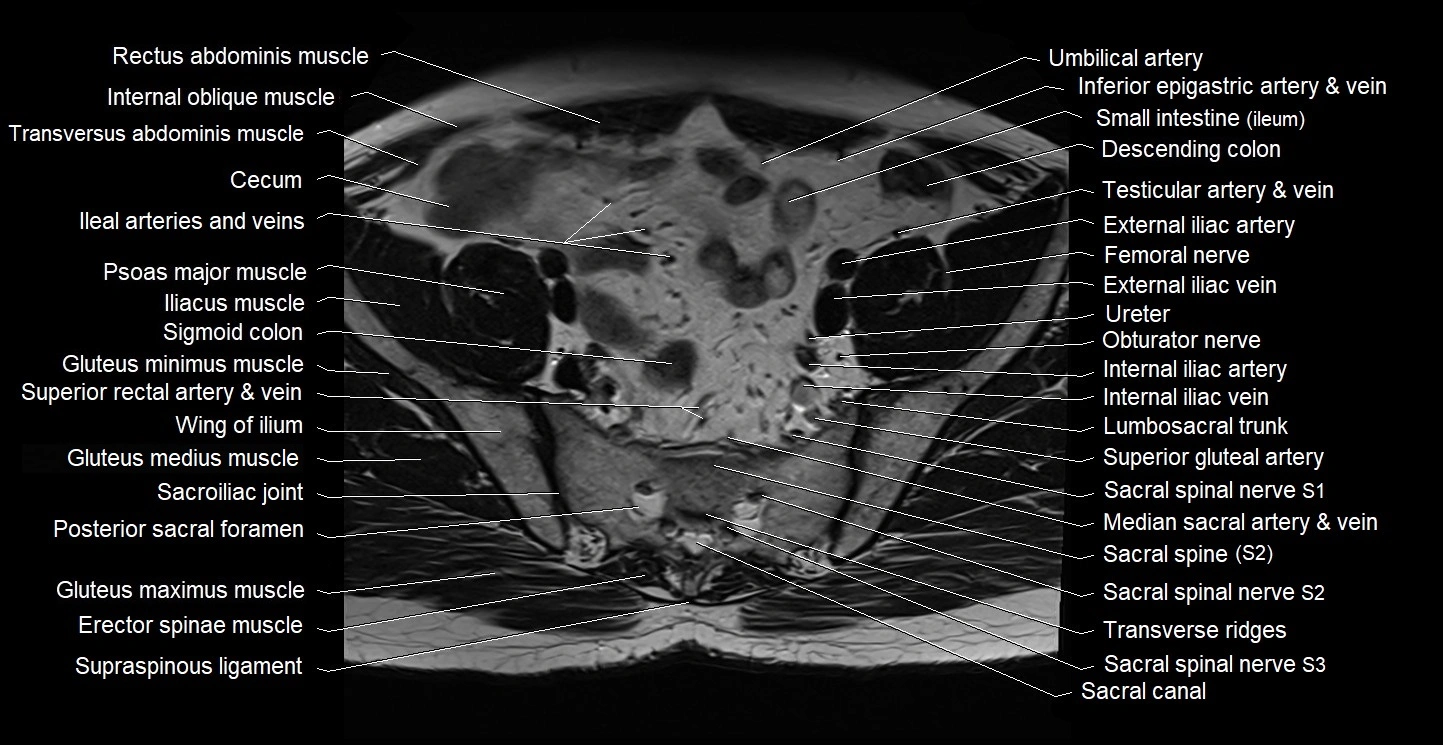

- Cecum

- Erector spinae muscles

- Gluteus maximus muscle

- Gluteus medius muscle

- Gluteus minimus muscle

- Internal iliac artery

- Internal iliac vein

- Lumbosacral trunk

- Sacroiliac joint

- Sigmoid colon

- Spinal nerve S1

- Spinal nerve S2

- Spinal nerve S3